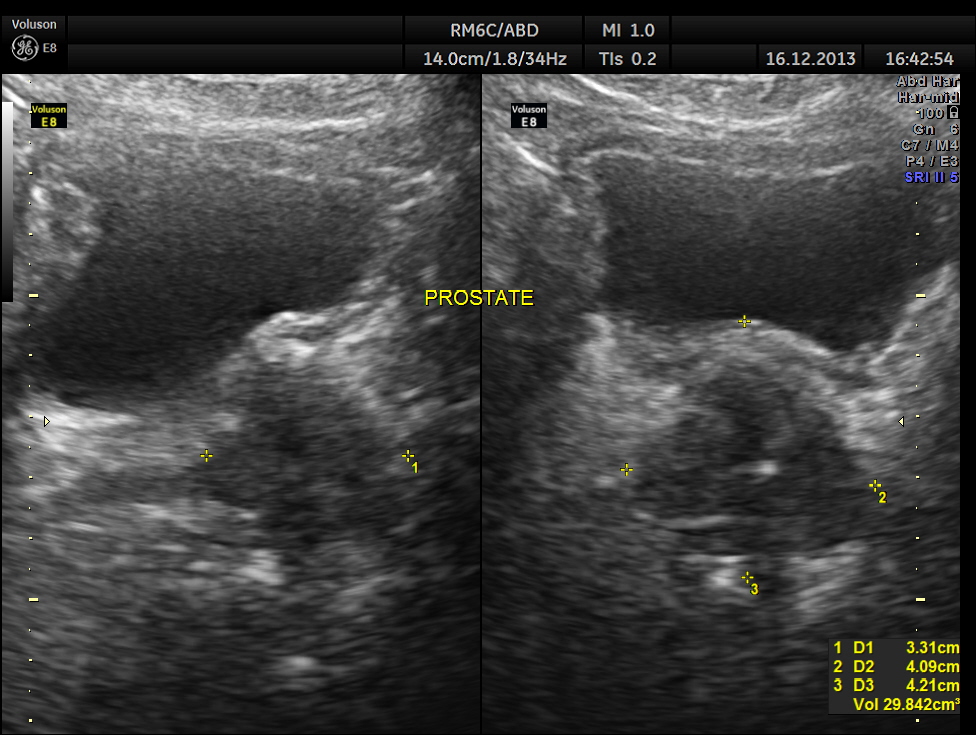

He also had mild prostatomegaly.